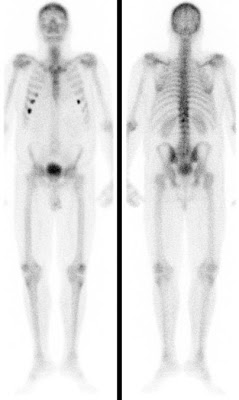

Bei der Skelettszintigraphie werden schwach radioaktiv markierte Phosphatkomplexe verabreicht, die zunächst im Blut durch den Körper zirkulieren und im Verlauf von 2-3 Stunden ausreichend in den Knochen eingebaut werden, so dass dann der Knochenstoffwechsel abgebildet werden kann.

Es bestehen die Möglichkeiten, gleich nach Verabreichung der Phosphatkomplexe die Durchblutung zu untersuchen und auf den Spätaufnahmen den Knochenumbau zu beurteilen. Bei der Skelettszintigraphie gibt es keine Unverträglichkeitsreaktionen auf die verabreichten Radiopharmaka. Im Gegensatz zu vielen Röntgenkontrastmitteln sind die verwendeten Radiopharmaka auch nicht nierenschädlich.

Die Hauptfragestellungen bei der Skelettszintigraphie betreffen die Feststellung evtl. Knochenmetastasen bei Krebserkrankungen und die Unterscheidung von primär entzündlichen vs. primär degenerativen Gelenkerkrankungen, also rheumatischen Grunderkrankungen mit Skelettbeteiligung vs. (aktivierten) Arthrosen.

Darüber hinaus ist die Skelettszintigraphie häufig auch bei der Abklärung unklarer Knochenschmerzen sehr hilfreich, etwa zur Feststellung evtl. Knochentumoren, von Prothesenlockerungen, einer Osteomyelitis, von Frakturen, von Knocheninfarkten etc.